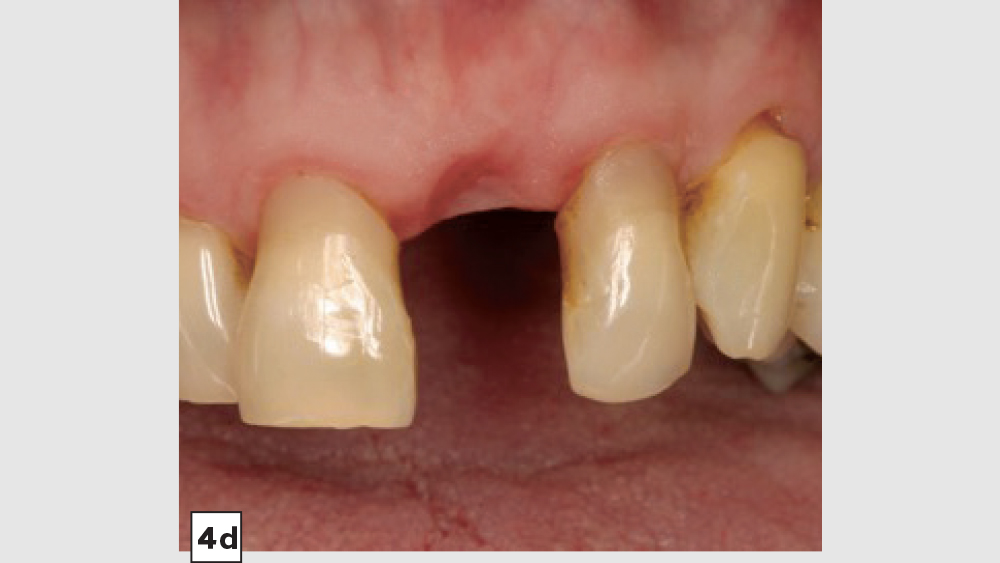

Four-Walled Socket Bone Grafting Technique (Figs. 4a–4d, 5a–5c)

1. Reflection: In most four-walled sockets, a partial mucoperiosteal flap should be reflected to allow for surgical access to the missing buccal plate. This will allow the clinician to place a membrane properly along the buccal plate.

5. Closure: Closure should be completed with a 3-0 or 4-0 high-tensile suture material (e.g., PGA or PTFE) with a crisscross suture technique. Care should be exercised to avoid suturing through the membrane. Gut sutures (plain, chromic) should be avoided, as they have a compromised tensile strength and incision line breakdown may occur.